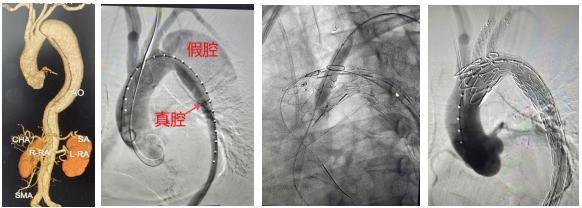

影像图

因此,瑞康医院心内科团队决定通过主动脉支架体外开窗方法保住左锁骨下和左颈总动脉,根据术中测量结果和3D打印模型,选择主动脉覆膜支架体外开窗,取左颈总动脉及左锁骨下动脉开窗并缝内分支支架一枚,同时行支架束径。其间,自右股动脉入路送入主动脉支架至弓部预定位置半释放,分别经左颈总动脉及左肱动脉入路,导丝配合导管超选开窗洞口至主动脉支架内,沿导丝送入两枚分支支架,分别释放主动脉及分支支架。

术后,造影显示各分支动脉畅通,夹层完全消失无内漏。手术完美结束。

主动脉夹层是一种极其危险的心血管急症,主要表现为突发性剧烈胸背痛。这种疾病就像轮胎内胎破了个口子,血液从血管最内层(内膜)的破口冲进血管壁中间层,像吹气球一样把血管壁撑开形成血肿,随着血液不断冲击,血管壁的内层和中层被撕裂分离。此时,血管被撕开形成真假两个通道,即真腔和假腔,两者之间被撕裂的血管壁(内膜片)隔开。